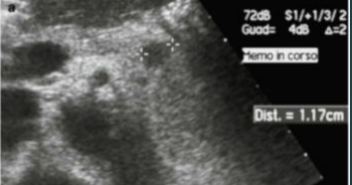

Acute pancreatitis with stone obstructing the pancreatic duct

Describe this image

Diagnosis?

Gallbladder with wall thickening and a stone obstructing the common bile duct causing dilatation (posterior shadowing). Results in pancreatitis

Dx: gallstones/pancreatitis